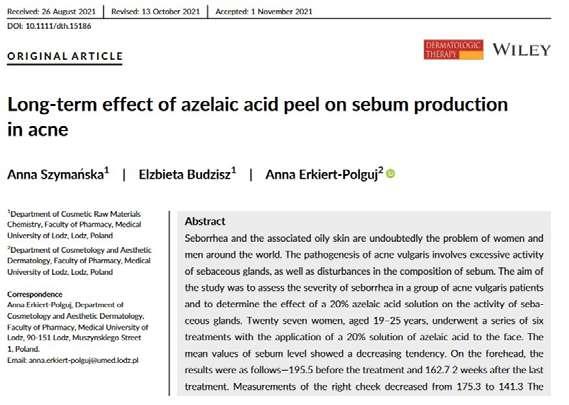

Let us look at two of them. The first, published in 2022 in the journal Dermatologic Therapy, is called: Long-term effect of azelaic acid peel

on sebum production in acne.

In the study, cases of seborrhea combined with acne were explored, with the aim of examining how 20% azelaic acid peeling affects the rate of sebum secretion and how both seborrhea and acne are affected by a series of treatments. 27 women, aged 19-25, underwent a series of 6 treatments at an interval of two weeks. Sebum secretion levels were measured using a special measuring device, before the treatments, two weeks after the last treatment and 3 months after the end of the experiment. It was found that the sebum secretion level decreased when measured two weeks after the last treatment: a decrease of 17% in the forehead area and 19.5% in the cheek area.

And even more interesting - 3 months after the end of the experiment, another decrease was measured: 22% in the forehead area and 21% in the cheek area! In addition, an improvement in the

acne and seborrhea indices was measured - fewer acne lesions with a delay in the appearance of new lesions, and a decrease in the severity of the seborrhea disease.